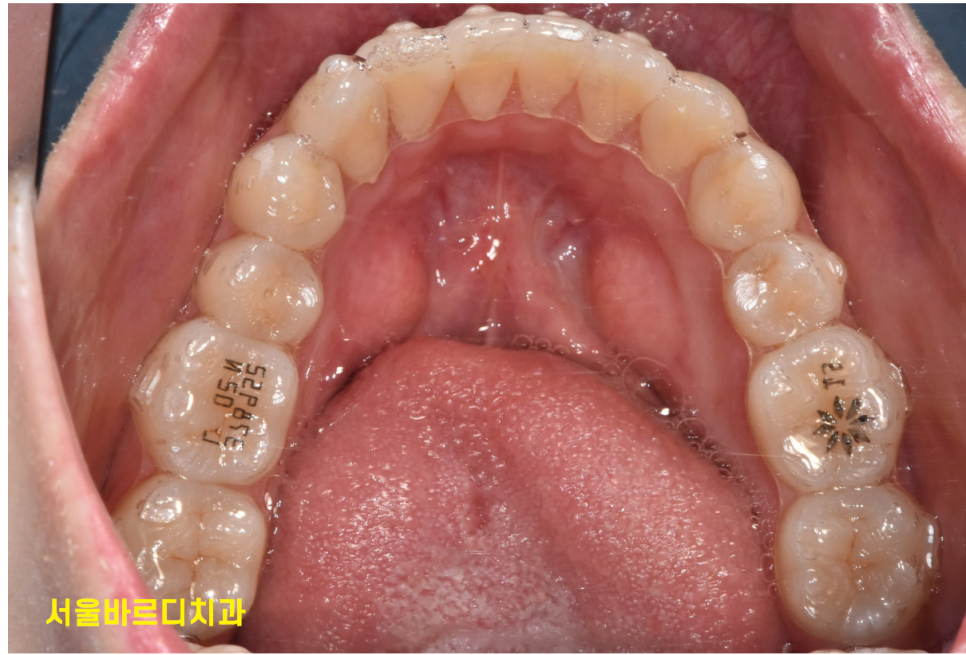

230909 장치를 꼈는데 전혀 티가 안나죠?

내원을 자주 안해도 되니까!!